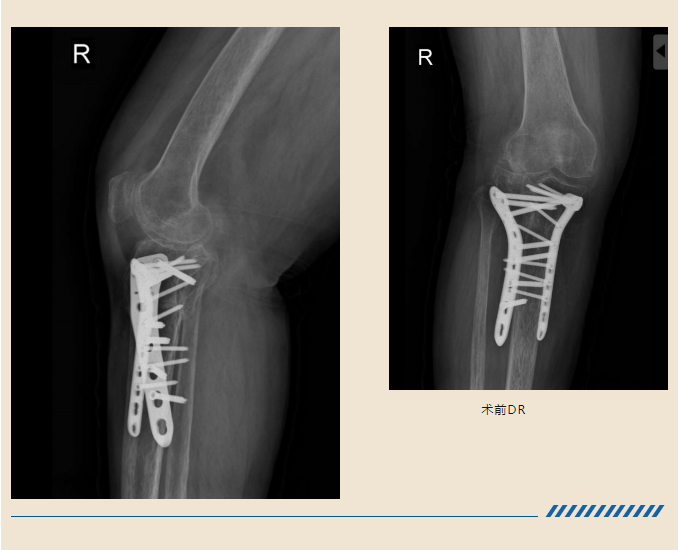

造成了右腿的胫骨平台骨折

在当地医院手术治疗后

结果却不尽人意

骨折部位畸形愈合

手术需要将畸形愈合的骨头

重新断开

恢复力线和关节面平整